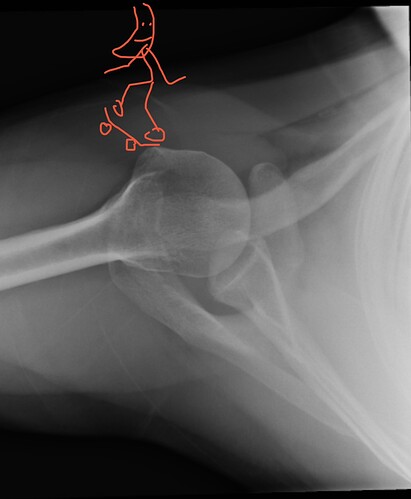

Pic of me bout ta drop in and fall on my ass: